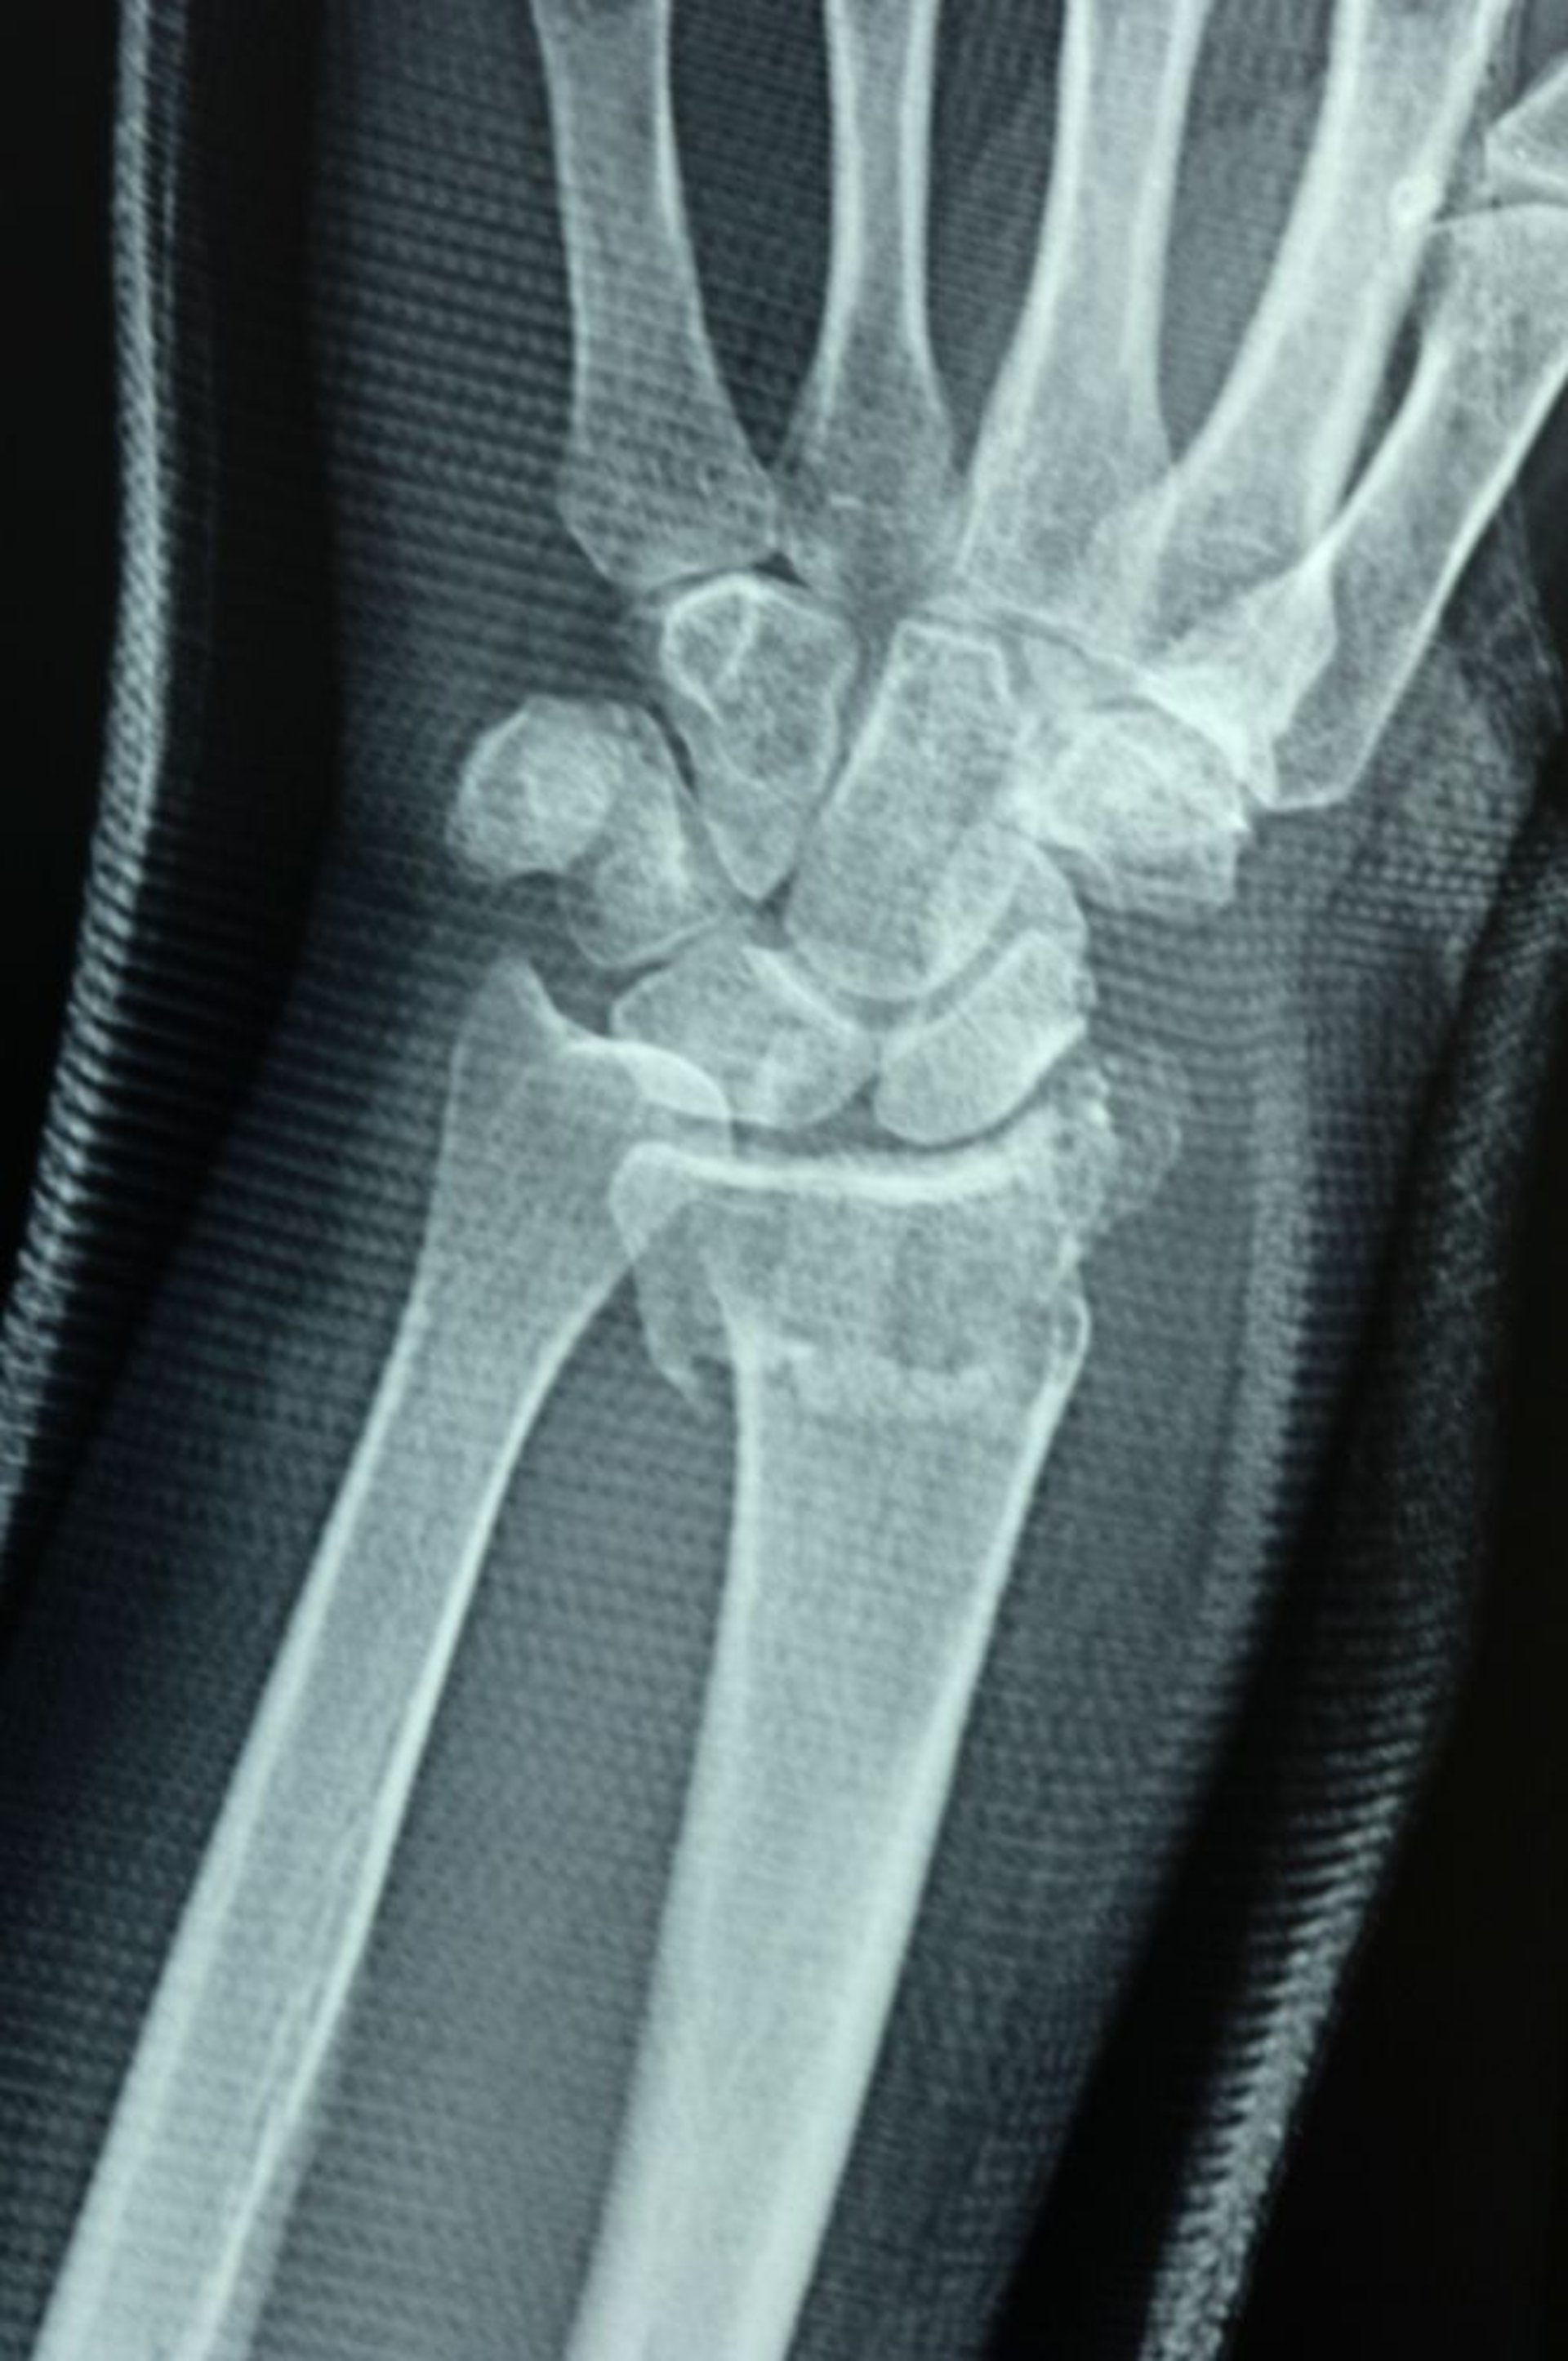

Fracture distale du radius

L'articulation radioulnaire est lésée, comme en témoigne l'échec de l'alignement des surfaces articulaires du radius distal et du cubitus distal, qui provoquent une discontinuité.

DR P. MARAZZI/SCIENCE PHOTO LIBRARY